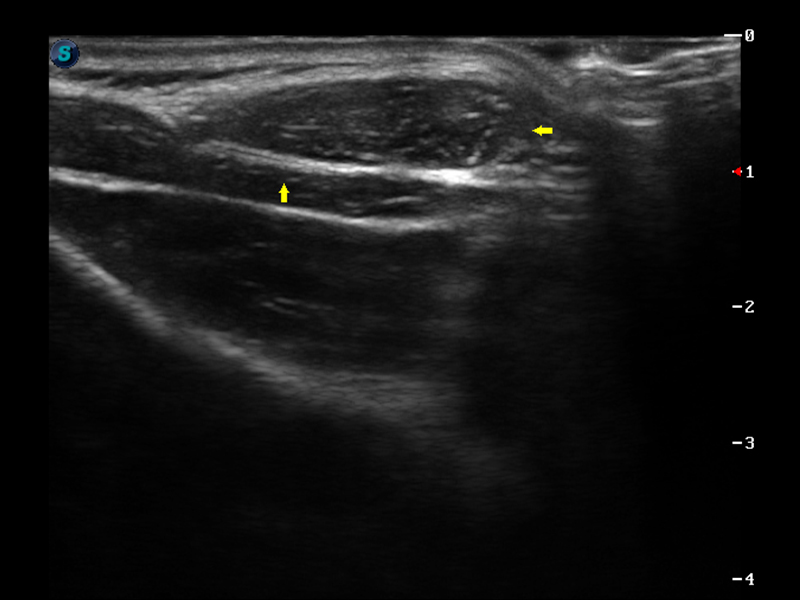

S9便携式彩色多普勒超声诊断仪是乐玩lewin国际研发的高端便携彩超设备,外观设计新颖、产品性能卓越。S9在便携超声领域采用了突破传统的触摸屏交互设计,并以先进的软件硬件技术和设计理念,为您带来清晰的图像质量、稳定的工作性能和便捷的操作体验。

μ-Scan微米成像

实时宽景成像